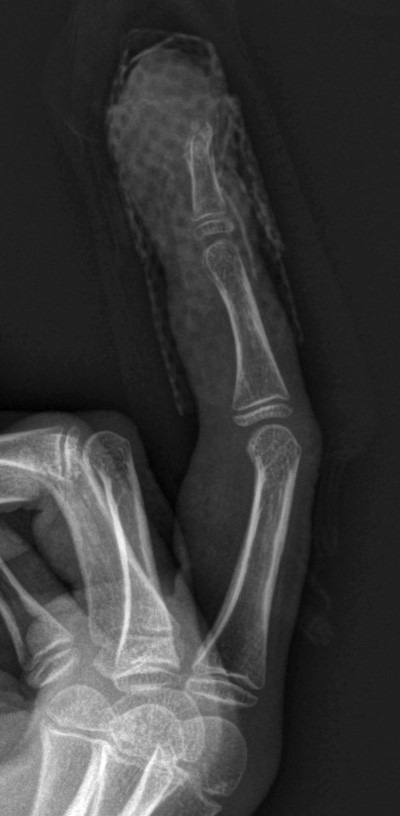

Da fingeren ikke ble bedre, ble han henvist til ortopedisk avdeling ved lokalsykehuset. Såret ble revidert, og etter prøvetaking til mikrobiologisk diagnostikk ble det startet antibiotikabehandling med dikloksacillin. Det var ingen oppvekst av bakterier eller virus. Biopsi viste reaktive forandringer. Røntgenbilde av høyre hånd viste erosjon av distale falang på 3. finger. Det var ingen andre funn i skjelettet.

Det ble tatt nye mikrobiologiske prøver, ny biopsi i ledningsanestesi og røntgen- og MR-undersøkelse av finger og hånd. Gutten ble utskrevet fra hudavdelingen i påvente av resultatet fra den nye biopsien. Røntgen viste destruksjon ytterst i ytterfalangen (fig 2). MR viste en bløtdelsoppfylling ytterst på 3. finger som målte 15 × 15 × 18 mm. Det var infiltrasjon i hud og beinmargsødem i resten av ytterfalangen (fig 3). Den nye biopsien viste tallrike blodkar og epitel med mye granulocytter. Det var ingen tegn til mitoser eller neoplasi.